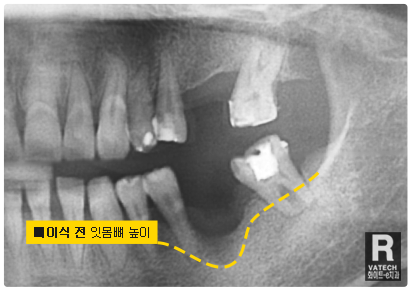

:: 엑스레이 촬영을 통하여 살펴보는 뼈이식 & 임플란트 ::

공간 확보를 위한 엑스레이 촬영

이렇게 임플란트 인공치아 뿌리를 식립하려 하는 자리에

엑스레이 촬영을 통해 공간을 먼저 봅니다.

잇몸뼈 소실 복구

자~ 눈금으로 쉽게 표기해 드릴게요.

보시다시피 옆자리의 잇몸뼈의 높이보다 상당히 내려가

있습니다. 치아가 자리에 없는 동안 많은 잇몸뼈 소실이

원인입니다.